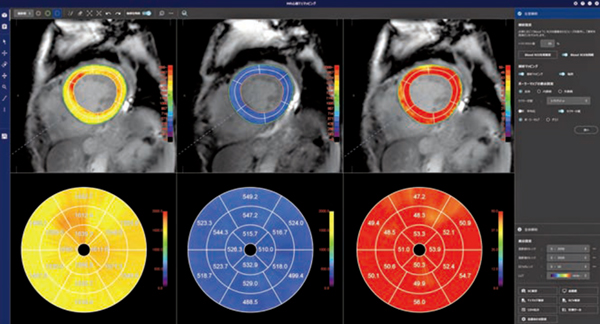

REVORASの「MR心筋T1マッピング」では,データを開くと非剛体位置合わせやinversion time(TI)間の位置ズレ,造影前後の位置ズレの補正が自動で実行される。左室解析ステージでは,左室内腔と外壁の自動抽出を基にセグメントごとのT1値の評価を確認でき,native/enhanced/ECVのセグメントごとの解析結果がポーラーマップ上に表示され,同時に観察することができる。全体解析ステージでは,画像全体に対するT1値の算出や,関心領域の設定による任意の領域のT1値評価を簡便に行うことが可能である。解析ワークフローの改善によりデータオープンから解析結果表示までの時間短縮が図られ,新たなバージョンからはレイアウトも一新し,より効率的に解析業務をサポートする(図1)。

図1 MR心筋T1マッピング